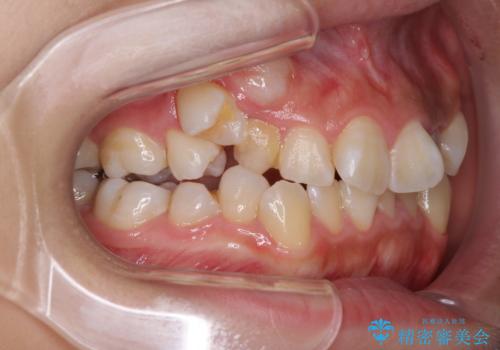

- 前歯のでこぼこと乳歯が残るほどの八重歯を気にして来院された患者様です。

非抜歯にてワイヤー矯正にて治療することとしました。(ただし、親知らずと乳歯は抜歯)

犬歯は歯根が太く長いため、移動には時間を要します。しかし、犬歯は機能面から考えて残すことを選択したいため、長期間をかけて治療を行うこととしました。